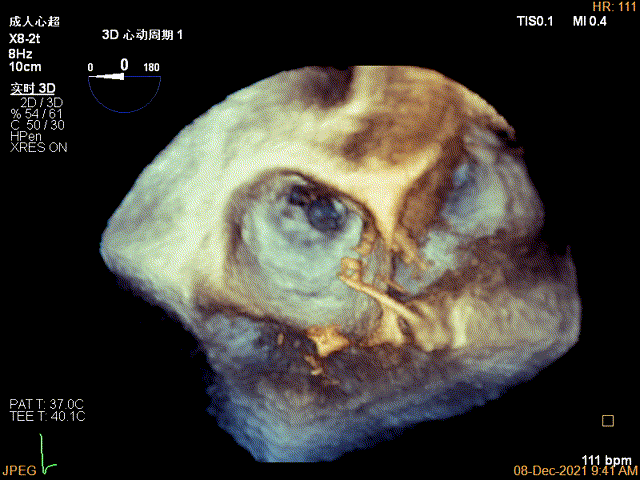

3D视图菲薄的卵圆窝,穿刺点位近似于3点位

3D视图下大鞘位置及长度测量